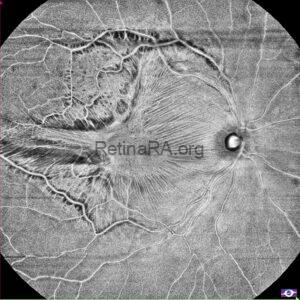

Gravitational tracks in chronic central serous chorioretinopathy: a multimodal imaging case

Patient history A 34-year-old male patient with a history of chronic central serous chorioretinopathy (CSC) [...]